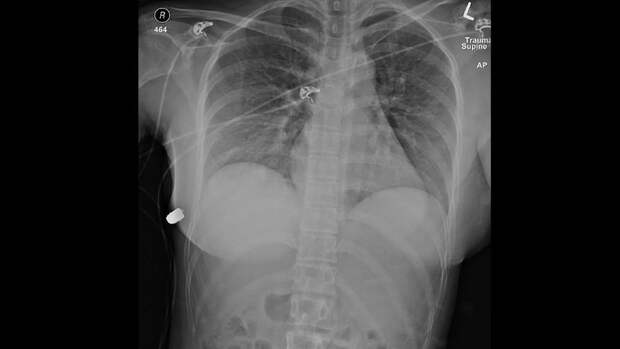

Пуля застряла в нижней части грудной клетки, справа, под грудью. Она прошла через силиконовый имплант левой груди, перевернула правый вверх ногами и сломала правое ребро.

Удалив импланты и очистив рану, врачи на всякий случай назначили пациентке антибиотики. Она достаточно быстро восстановилась, не столкнувшись ни с какими осложнениями.

Врачи отмечают, что без имплантов ситуация была бы гораздо хуже - учитывая траекторию пули, она могла бы попасть в сердце и женщина бы погибла на месте.